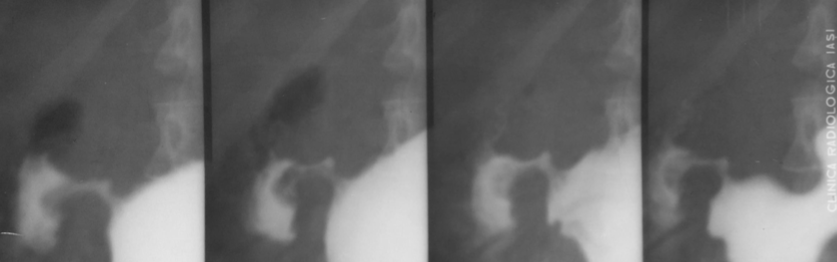

Volvulus gastric